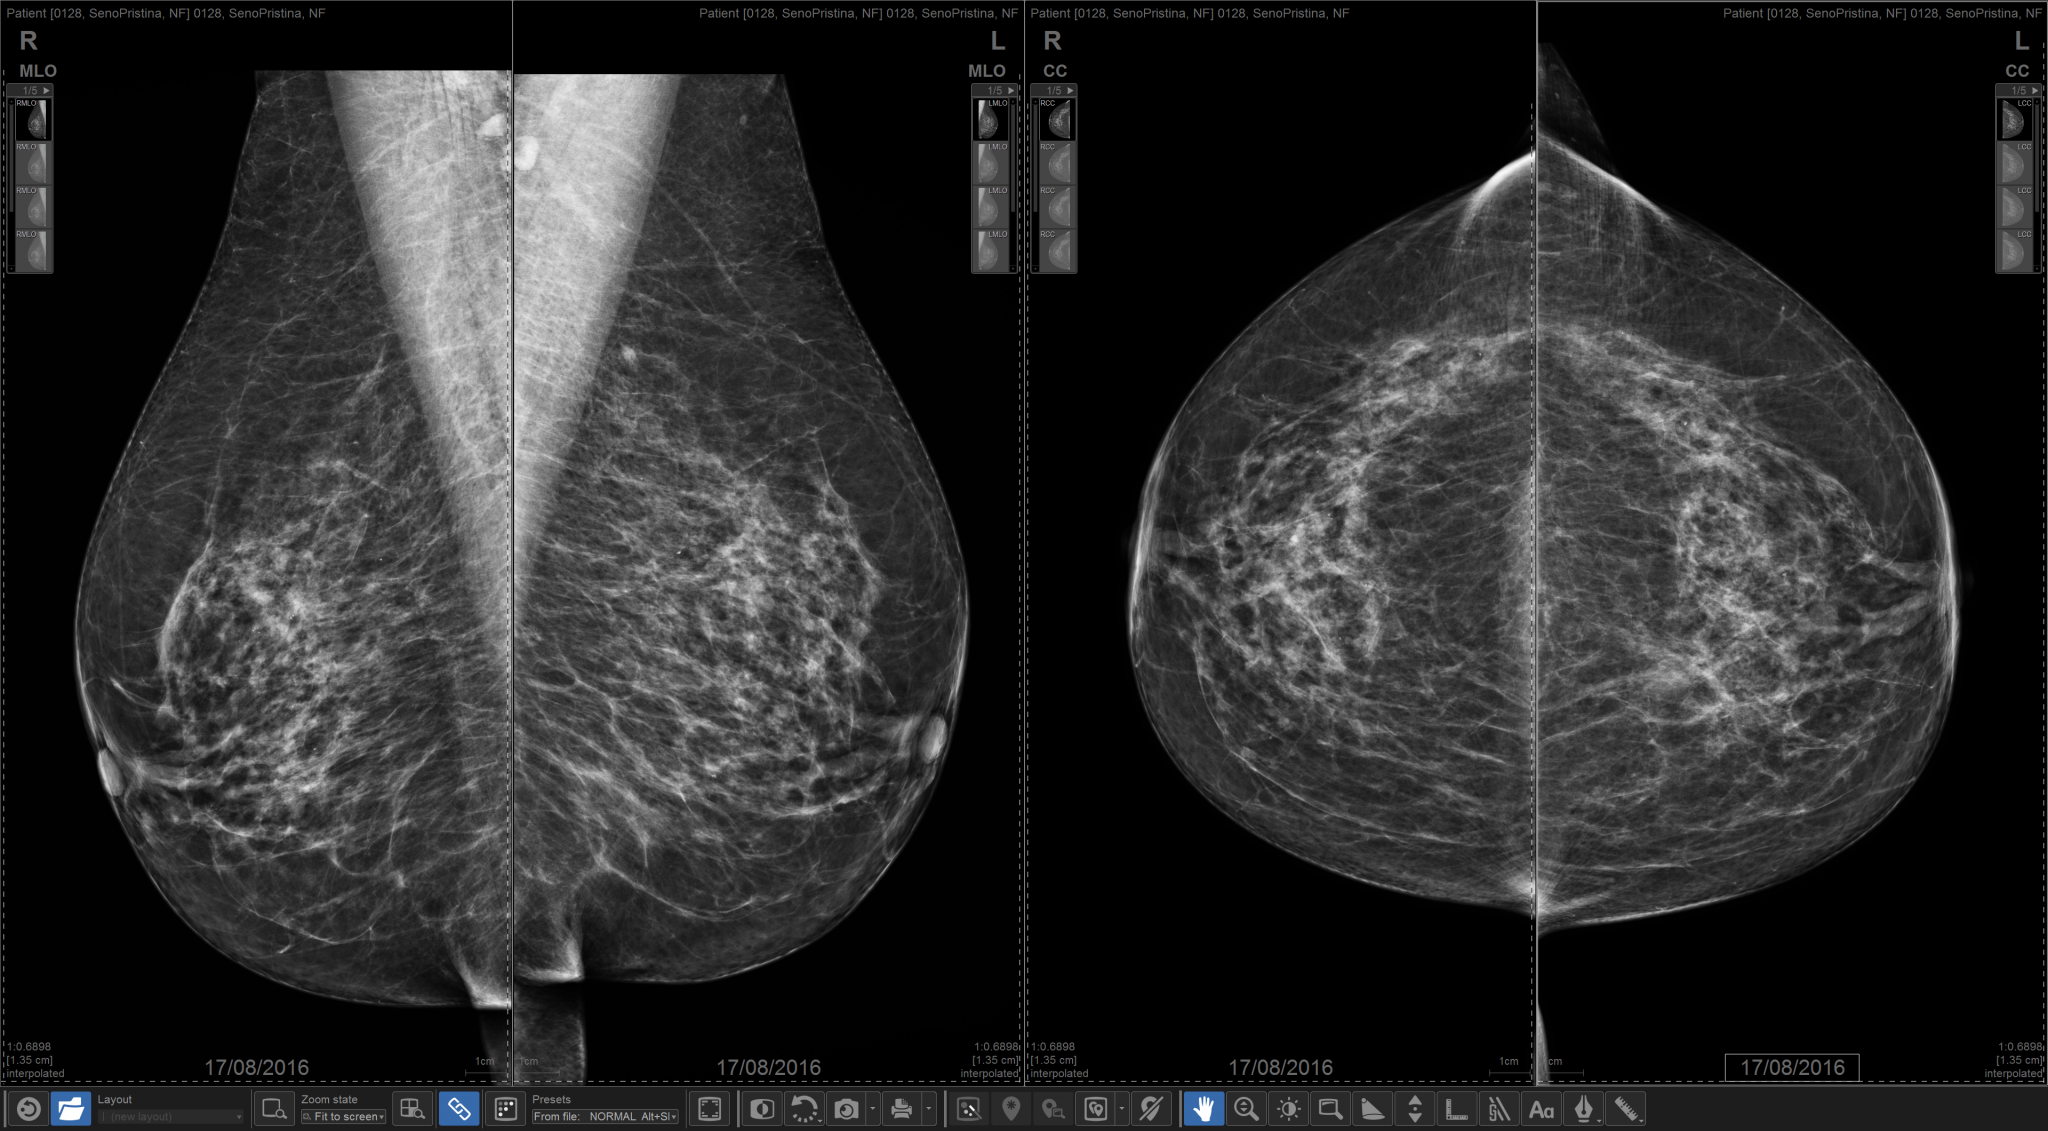

Mammograms for breast pain in 78% of patients.

94% of which were diagnostic mammograms

A mammographic finding in the area of breast pain was seen in four of 625 mammograms.